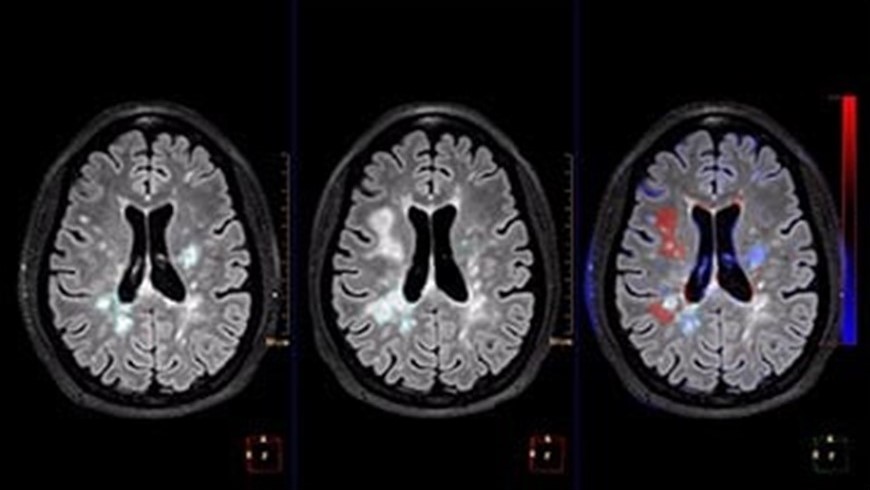

Philips IntelliSpace Portal for MRI Neuro

PHILIPS